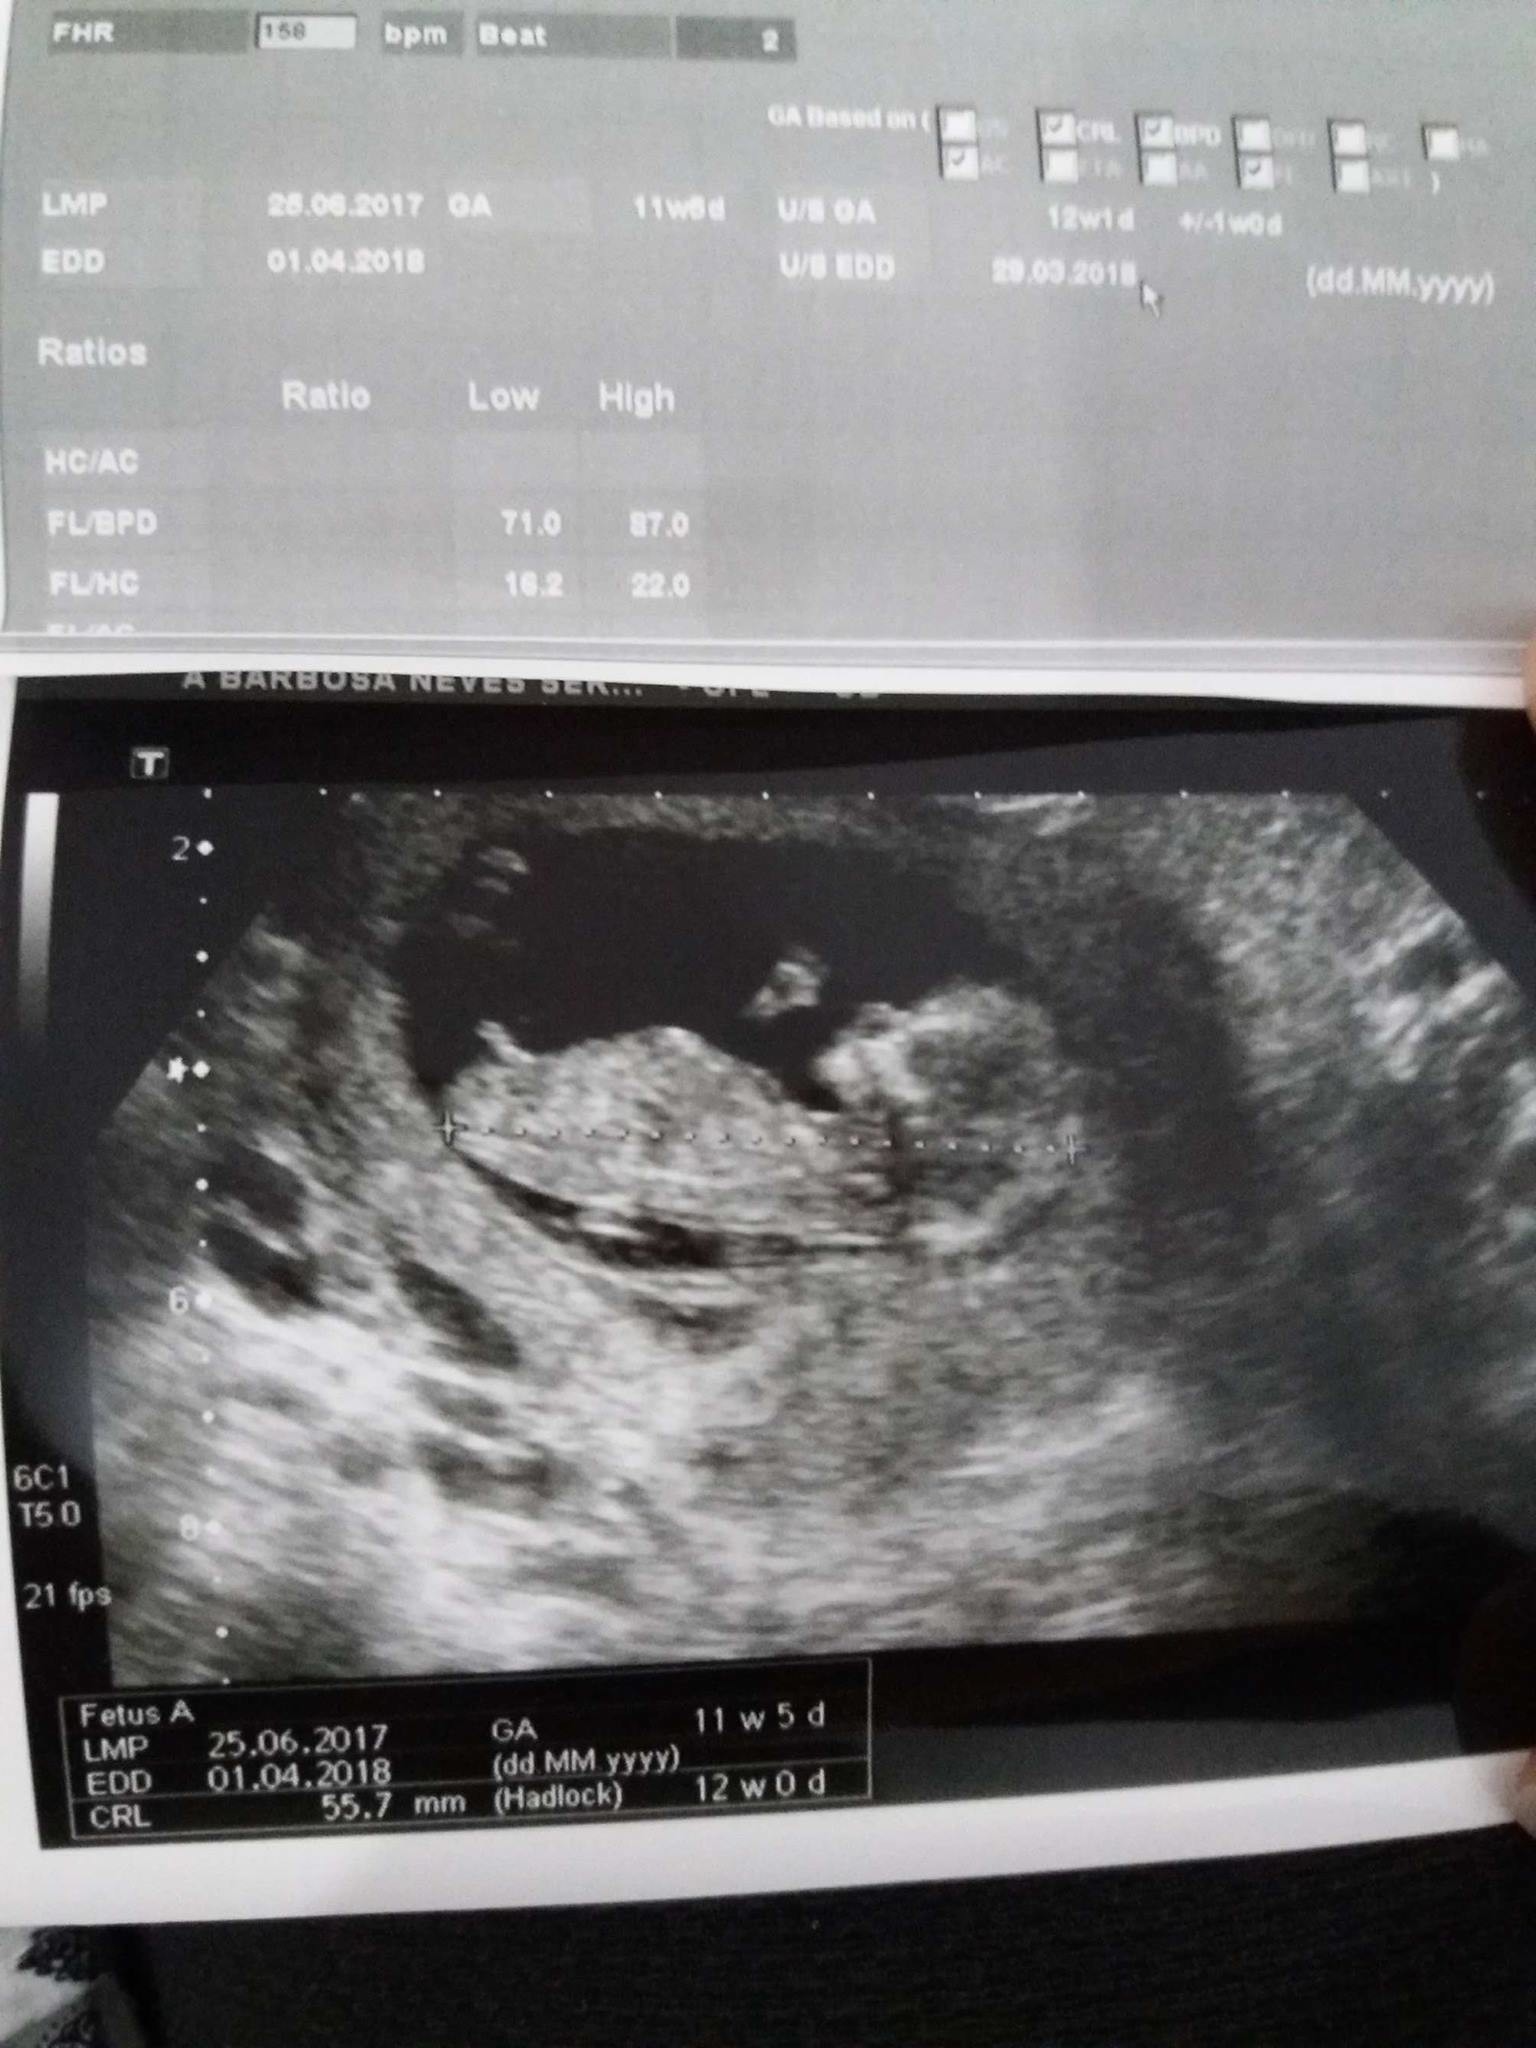

Ainsi une échographie endovaginale peut déterminer si cette grossesse se développe normalement quil ny a pas de risque de fausse couche et que lembryon se développe correctement à l. Donc la date de fécondation est donc entre le 12 et le 26 octobre. Mais encore une fois laspect est parfois trompeur.

Dans tous les cas léchographie est totalement indolore et rapide. Certains tests sanguins sont en revanche obligatoires pour la femme enceinte comme la rubéole la toxoplasmose et lHépatite B. Tu auras des tas de témoignages qui te diront que les erreurs existent mais ça ne te dira pas si cest une erreur pour toi ou pas.

Léchographie peut affirmer le diagnostic de syndrome de Rokitansky devant une aplasie vaginale par la mise en évidence dun noyau utérin rétro-vésical. Léchographie nest pas une science exacte cest pour cela que je vous donne ces 14 jours possibles. Vu que cétait un garçon à 17sg et cest bien un petit mec.